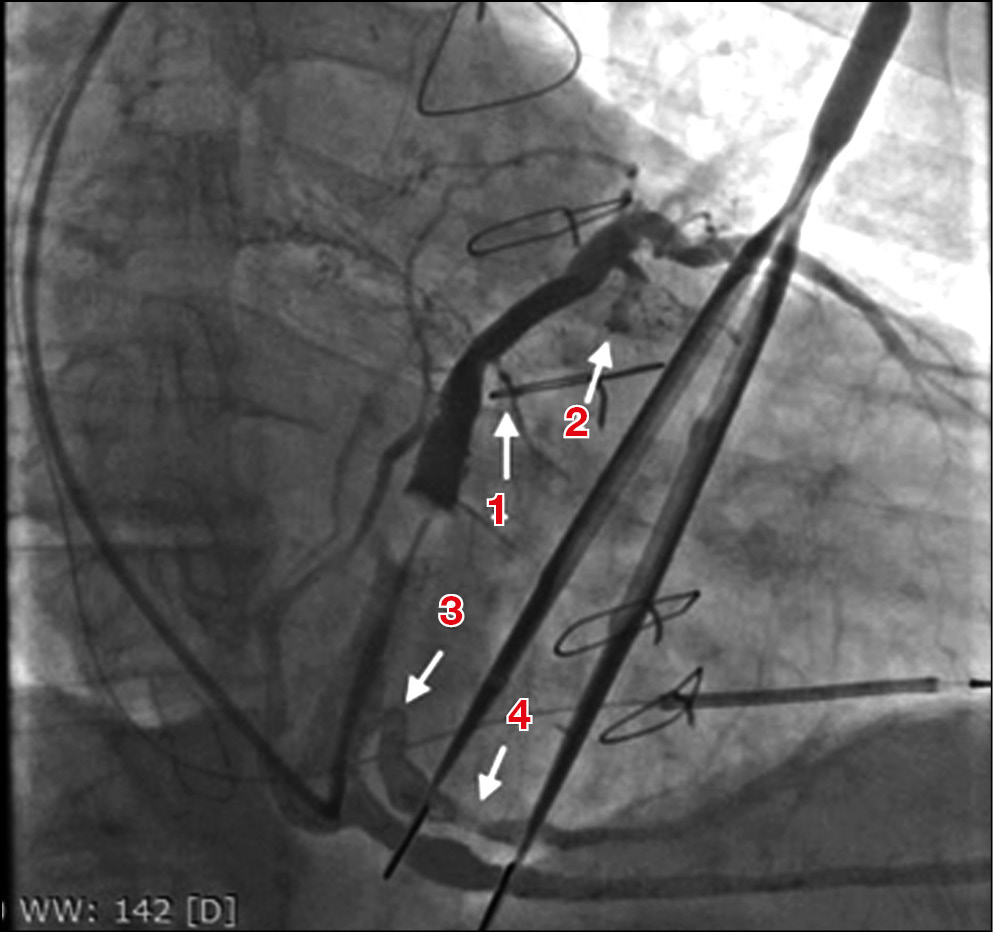

Интраоперационно состояние пациента стабильное. Имплантация ресинхронизирующего устройства проходила под местной анестезией раствором новокаина с доступом из левой подключичной области. Правожелудочковый электрод позиционирован в область верхушки правого желудочка стандартным способом. При позиционировании левожелудочкового электрода выполнено контрастирование венозной системы сердца, выявлено наличие латеральной вены сердца, которая считается оптимальной для имплантации левожелудочкового электрода. По данным рентгеноскопии, диаметр этой вены на всем протяжении был менее 1 мм (рис. 1). Переднелатеральная вена была достаточного диаметра в проксимальном участке на протяжении 1,5–2 см, затем нитевидно сужалась (см. рис. 1). Визуализирована достаточного диаметра заднелатеральная вена, отходящая от большой вены сердца на 2 см дистальнее устья средней вены сердца, идущая в область латеральной стенки левого желудочка. Заднелатеральная вена имела извитость (резкий изгиб) в проксимальном отделе и дефект наполнения, расположенный на 1,5 см дистальнее извитости, который, вероятно, обусловлен давлением на вену внешних анатомических структур (мышечный или соединительнотканный мостик). При этом интенсивность дефекта наполнения изменялась вместе с кардиоциклом: усиливалась в систолу, уменьшалась в диастолу.

Рис. 1. Интраоперационное контрастирование венозной системы сердца (правая косая проекция, 30°): 1 — нитевидная латеральная вена сердца; 2 — переднелатеральная вена сердца, нитевидно сужающаяся через 1,5–2 см от устья; 3 — резкий изгиб в проксимальной части заднелатеральной вены сердца; 4 — дефект наполнения, изменяющий свою интенсивность вместе с кардиоциклом, обусловленный, вероятно, внешним препятствием (мышечный/соединительнотканный тяж). / Fig. 1. Contrasting the cardiac veins during the operation (right anterior oblique projection, 30°): 1 — filiform lateral cardiac vein; 2 — anterolateral cardiac vein, very narrow within 1.5–2 cm from the vein orifice; 3 — sharp flexion in the proximal part of the posterolateral cardiac vein; 4 — a defect of filling in the posterolateral cardiac vein, its intensity changing with the heart cycle.